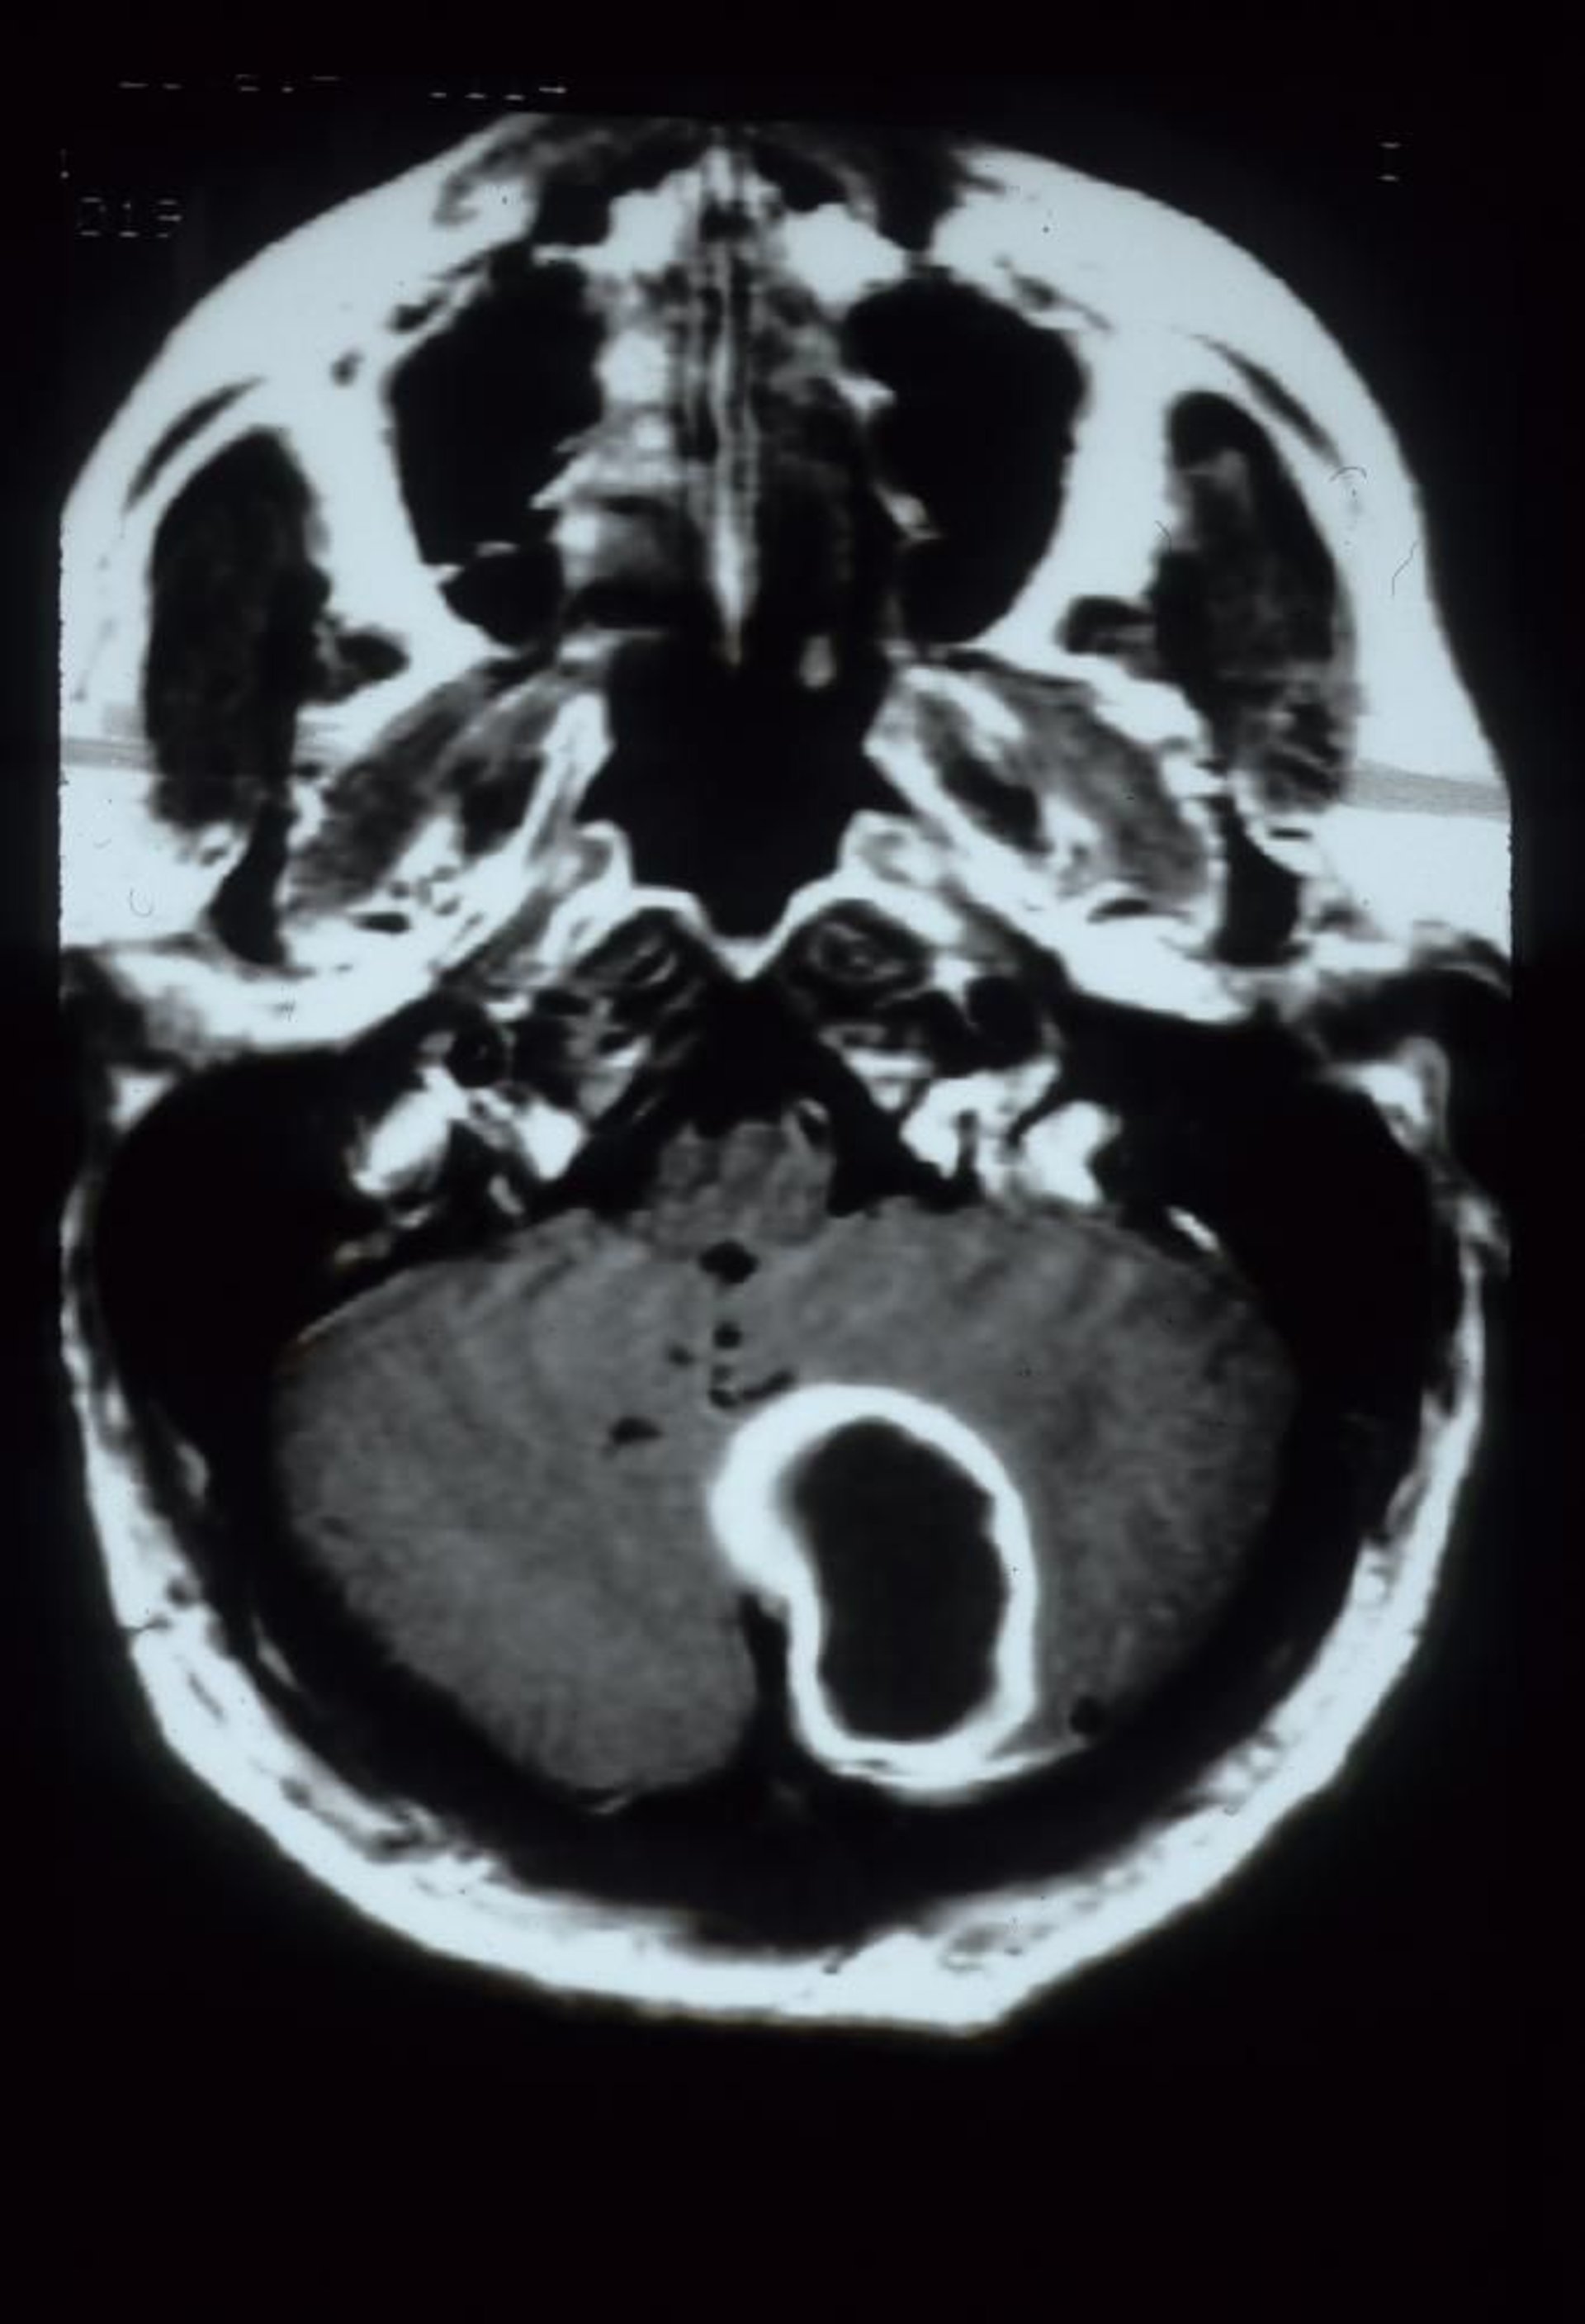

Cette IRM avec injection de gadolinium montre un abcès cérébelleux qui se présente sous la forme d'une lésion cavitaire de grande taille avec un contour qui prend le contraste dans l'hémisphère cérébelleux gauche.

Courtesy of John E. Greenlee, MD.